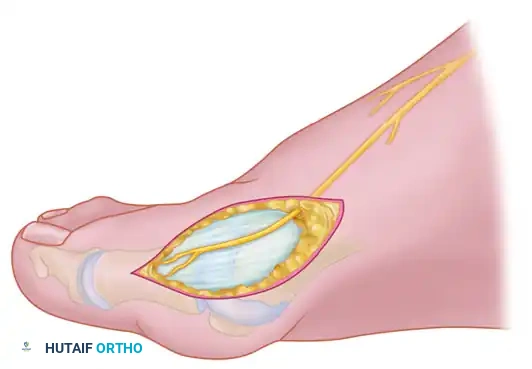

Fibular (Lateral) Sesamoidectomy: Dorsal Approach

In the modern Modified McBride procedure, the fibular sesamoid is rarely excised. However, if a severe, rigid valgus deformity persists after a complete adductor release and lateral capsulotomy, and the sesamoid cannot be mobilized, a fibular sesamoidectomy may be indicated.

- Adequately separate the first and second metatarsal heads using a lamina spreader or Inge retractor.

- Plantarflex the MTP joint 10 to 20 degrees to reduce tension on the sesamoid apparatus.

- Grasp the fibular sesamoid firmly with a small Kocher clamp or sturdy tissue forceps, pulling it laterally into the intermetatarsal space.

- Carefully release the intersesamoid ligament. Once incised, the fibular sesamoid can be delivered into the intermetatarsal space for straightforward removal.

- Surgical Warning: Extreme care must be taken when incising the intersesamoid ligament to avoid severing the flexor hallucis longus (FHL) tendon, which lies immediately plantar to it. If the FHL is inadvertently severed at this level, it generally should not be repaired, as repair often results in a rigid, fixed flexion contracture of the interphalangeal joint, whereas loss of the tendon causes minimal functional impairment.

- Alternative to Excision: Release part or all of the FHB lateral head at its insertion into the fibular sesamoid. Remember, performing both a metatarsal osteotomy and a fibular sesamoidectomy drastically increases the risk of iatrogenic hallux varus.

Fibular (Lateral) Sesamoidectomy: Plantar Approach

If the dorsal approach proves too difficult due to anatomical constraints, a plantar approach can be utilized for fibular sesamoidectomy.

- Have an assistant hold the ankle in dorsiflexion. A surgical headlight is highly recommended to visualize the full depth of the plantar wound.

- Flex and extend the hallux while palpating the plantar aspect of the foot to locate the sesamoid.

- Beginning 1.0 to 1.5 cm distal to the MTP joint, make a longitudinal incision on the plantar surface of the foot, extending proximally 3.5 to 4.0 cm between the first and second metatarsals.

- Separate the skin and fascial septa within the forefoot pad, and insert a small self-retaining retractor.

- Using small, blunt-tipped dissecting scissors, meticulously identify the neurovascular bundle to the first web space. Retract it laterally or medially, depending on the exact subluxated position of the sesamoid.

- Incise the plantar capsule and isolate the fibular sesamoid. Carefully shell it out from its soft tissue envelope, taking great care to protect the adjacent FHL tendon.